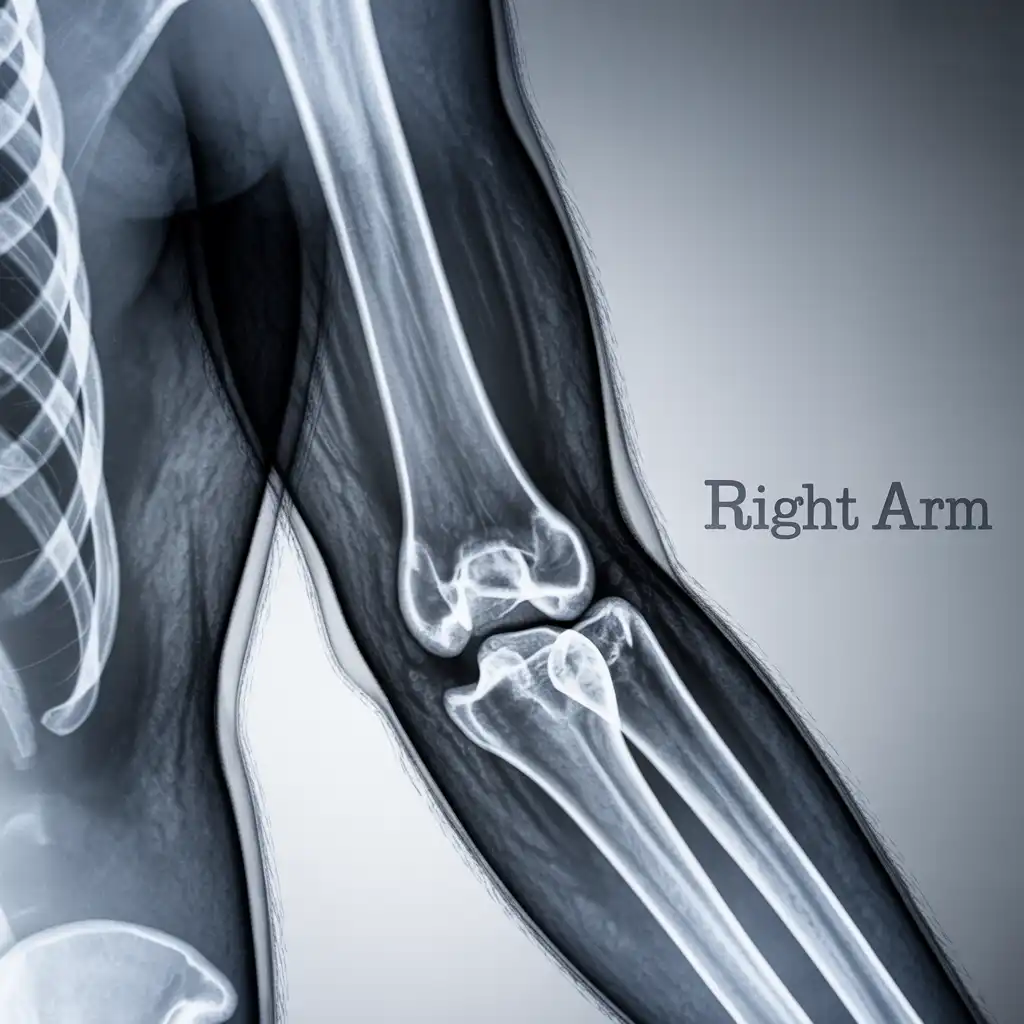

Una radiografia a domicilio è un esame radiologico eseguito da un tecnico specializzato che viene a casa tua con apparecchiature digitali portatili. L’esame si svolge sul posto, senza spostare il paziente e con la stessa qualità di una struttura ospedaliera.

Dopo l’acquisizione delle immagini, queste vengono inviate al medico radiologo che referta rapidamente e ti invia tutto in formato digitale. Un servizio comodo, sicuro e ideale per chi ha difficoltà negli spostamenti.